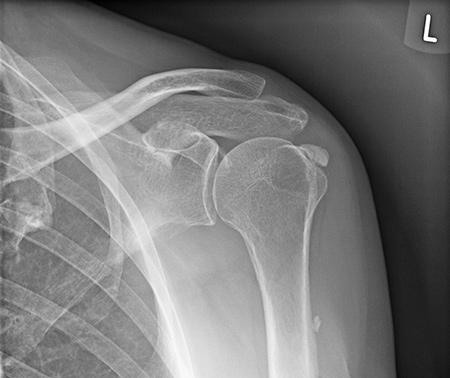

Abb. 1: ausgeprägte Kalkschulter im Röntgenbild

Wenn es zu einem Ungleichgewicht zwischen Resorption und Produktion kommt, kann sich der Schleimbeutelinhalt aufgrund seiner anatomischen Lage ungünstig entleeren. Die zähe Flüssigkeit nimmt nicht mehr teil am unmittelbaren Stoffwechselgeschehen des Gelenkes und kann sich in eine feste, poröse Struktur verwandeln. Das Krankheitsbild der Kalkschulter nimmt damit seinen Lauf. Die Diagnose wird am besten im Röntgenbild mittels einer sogenannten true ap Aufnahme von Ihrem Orthopäden gesichert.